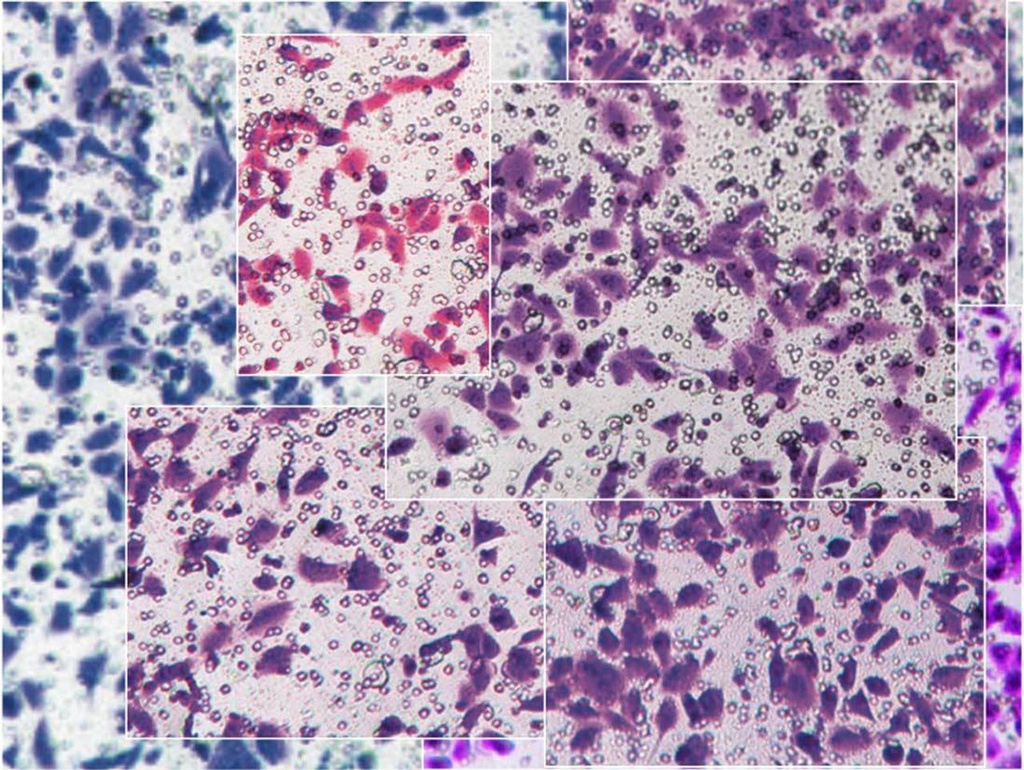

Cùng một ảnh chụp tế bào được sử dụng trong 7 nghiên cứu y khoa khác nhau do các tác giả Trung Quốc đứng tên. Ảnh: Elisabeth Bik.

Các bài viết được đăng tải rải rác trong vòng 4 năm bởi những tác giả khác nhau. Tuy nhiên, nhiều bài viết bao gồm ảnh chụp tế bào gần như giống hệt nhau dù tập trung vào các chủ đề nghiên cứu riêng biệt.

Những ảnh này đôi khi được xoay hướng nhìn khác hoặc cắt xén để tạo vẻ khác biệt. Chú thích hình ảnh đôi khi được dùng lại nguyên văn, không khác một từ.